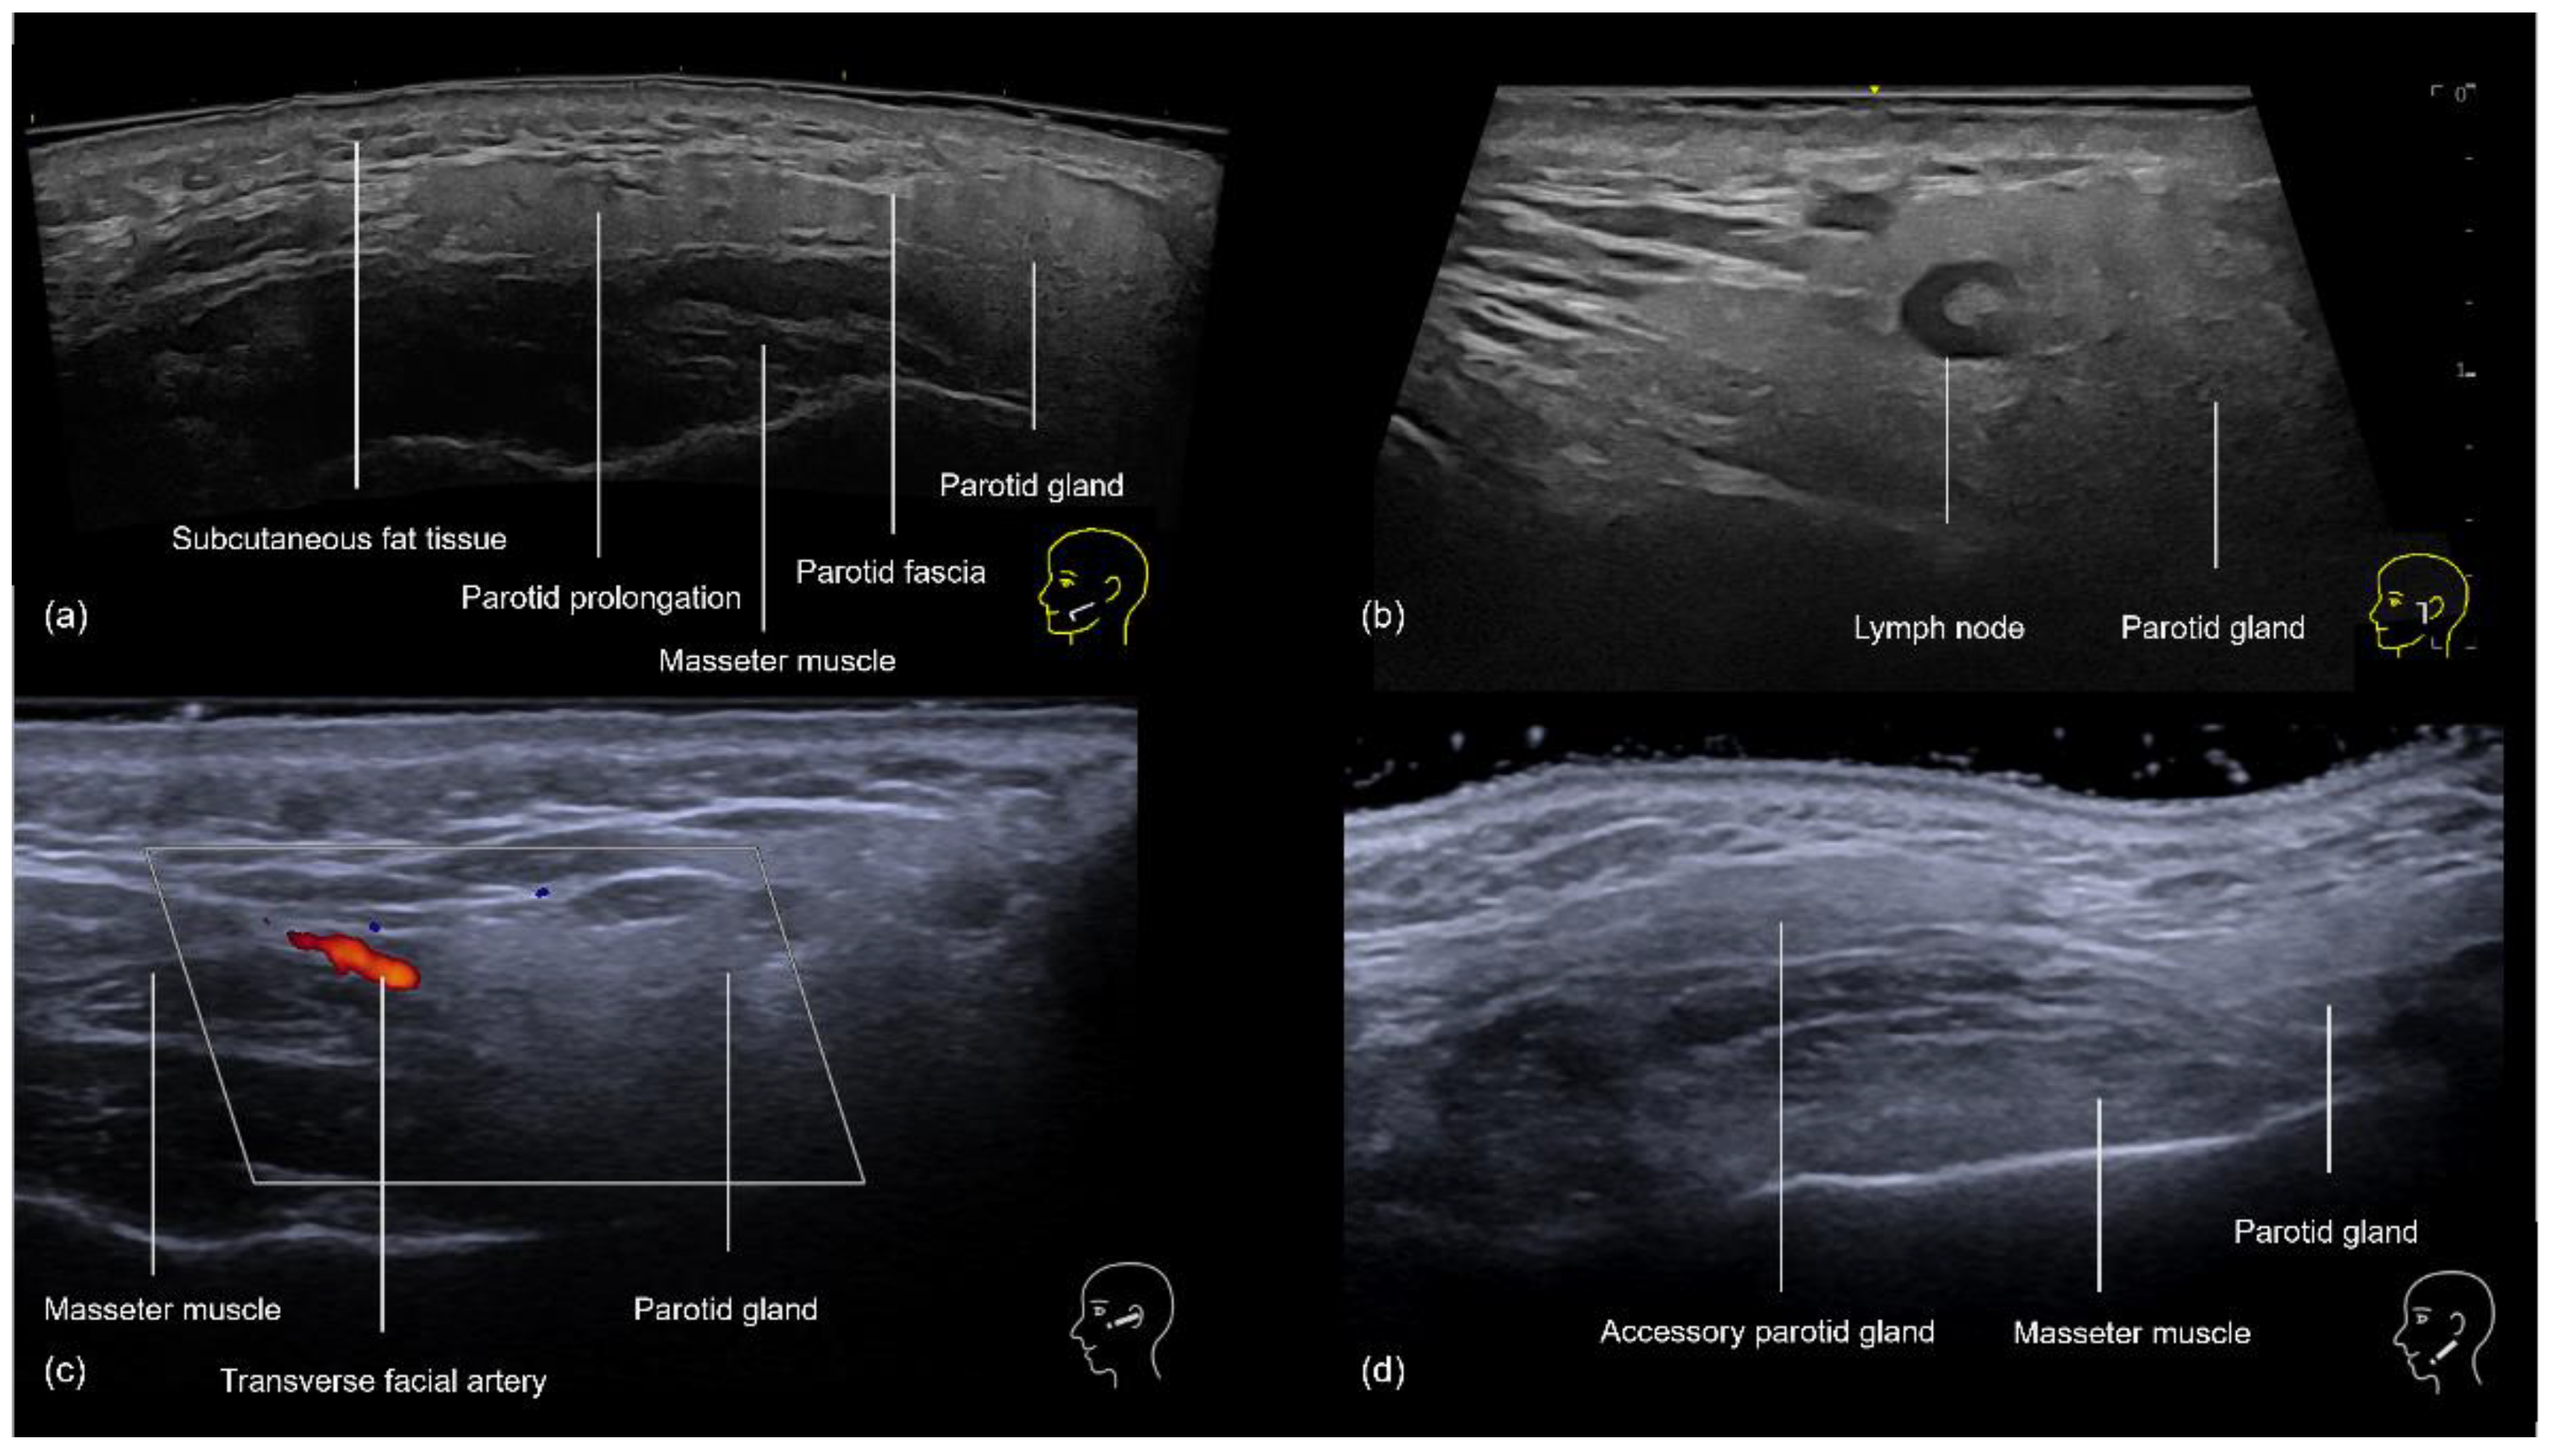

3.4.1. Sonographic Anatomy of the Zygomatic and Preauricular Region

3.4.2. Ultrasound-Guided Filling Techniques of the Zygomatic and Preauricular Region

- Preauricular Region